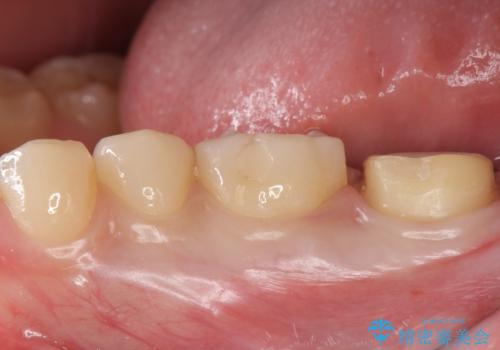

奥歯がしみる 神経を温存する治療

- 奥歯がしみるとのことで来院されました。

検査の結果、古い詰め物の裏側に虫歯ができていること(二次う蝕)が確認されたため、治療していくこととなりました。

- 左下7 生活歯髄療法:33,000円 仮歯+ジルコニアクラウン:11,000円+121,000円費用は治療当時の料金となります

虫歯が大きくても、今回のように神経を温存することができる場合があります。